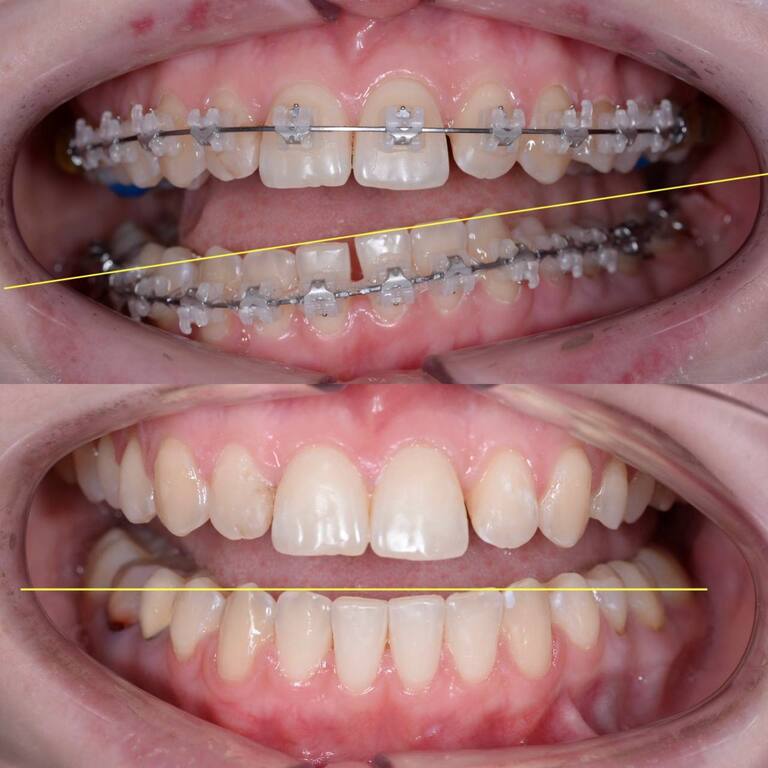

- straighten the dentition, correct the bite

ORTHODONTICS

Make your smile straight and white with help of aligners or brackets